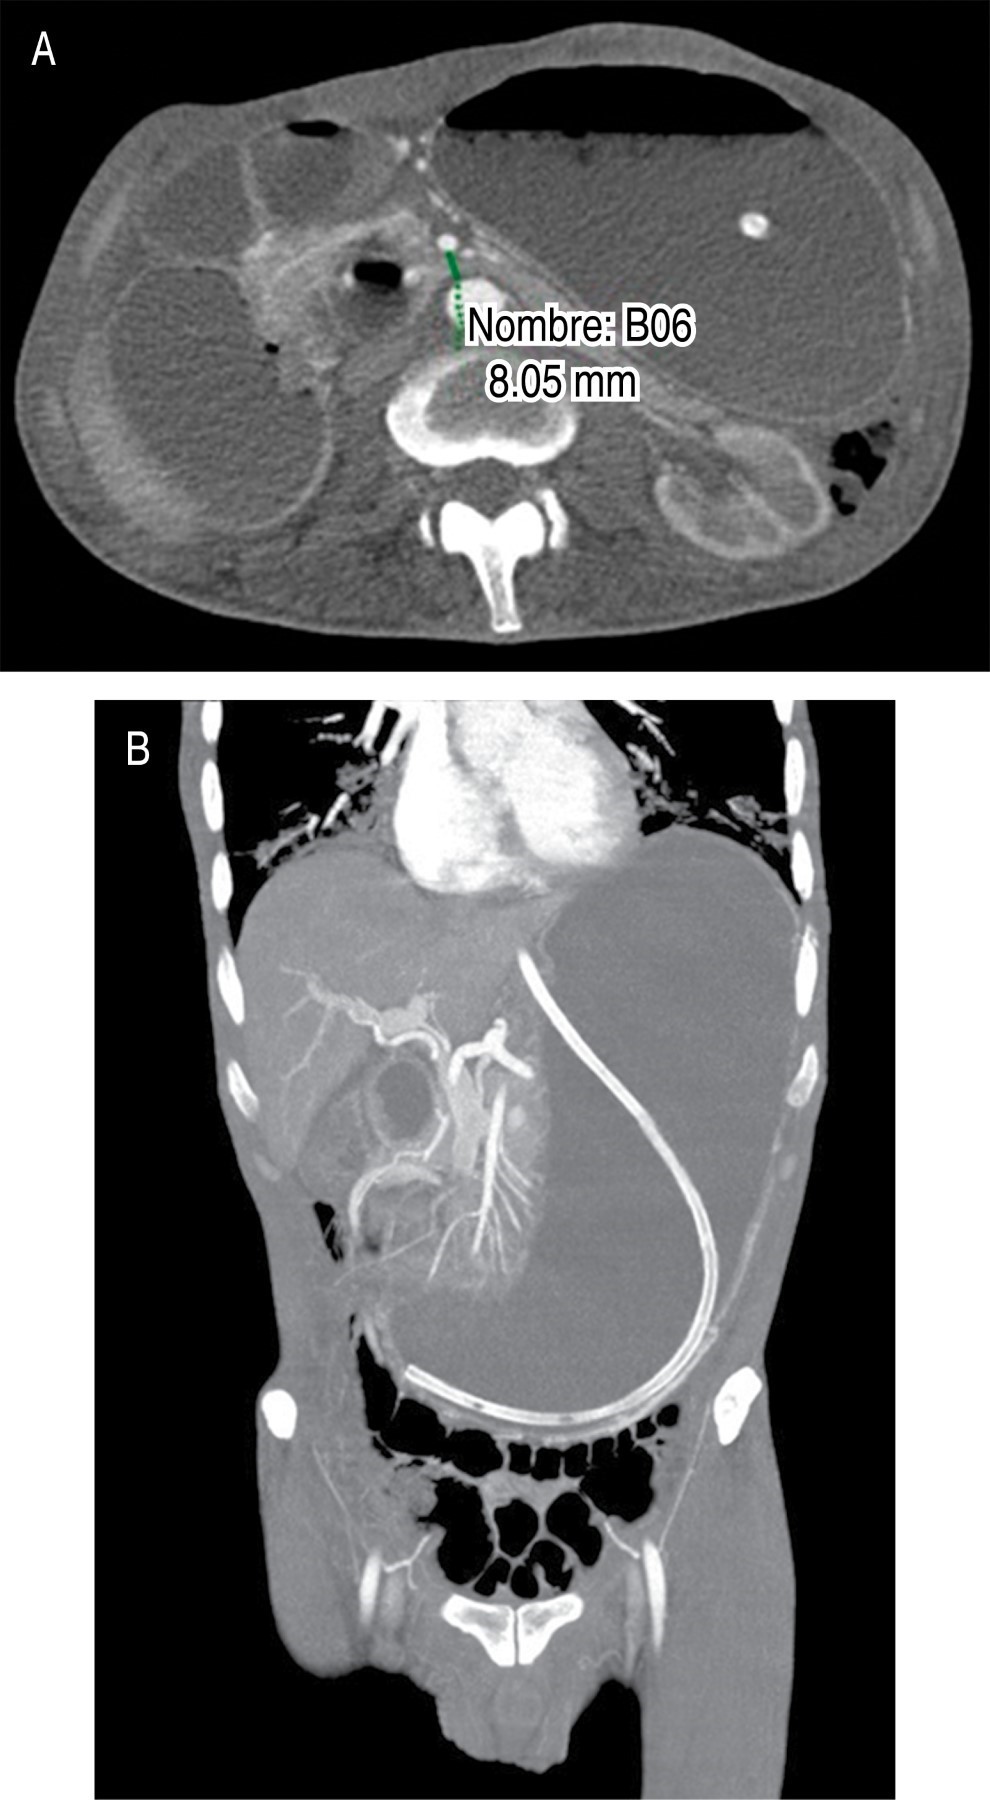

Se realizó tomografía de abdomen en la que se identifica dilatación gástrica con pérdida de los pliegues gástricos así como disminución de la distancia entre la arteria aorta y arteria mesentérica superior, la cual mide 8.05 mm (Figura 1). En el corte sagital de la tomografía se observa un ángulo agudo aortomesentérico de 14.92o (Figura 2). Desde su ingreso recibió manejo con descompresión gástrica con sonda nasogástrica, reposición hidroelectrolítica, analgésicos y antibioticoterapia con cefalosporinas de tercera generación; sin embargo, persiste la obstrucción a pesar de manejo conservador durante 48 horas, por lo que se propone y acepta manejo quirúrgico. Se realiza abordaje laparoscópico con cinco puertos, se moviliza el colon transverso y se visualiza el sitio de obstrucción secundaria a pinzamiento de la arteria mesentérica superior entre la tercera y la cuarta porción del duodeno. Se realiza duodenoyeyuno-anastomosis mecánica a 60 cm del ligamento de Treitz, se cierra gastroenterotomía en dos planos con monofilamento de absorción lenta para el primer plano y no absorbible para el segundo. Con buena evolución postoperatoria, inicio de líquidos a las 24 horas y progresión a dieta blanda a las 48 horas. Fue egresado por mejoría 48 horas después del procedimiento. En seguimiento postquirúrgico durante dos meses con adecuada tolerancia a la vía oral, no se cuenta con secuencia clínica posterior, ya que el paciente no asiste a control.

Figura 1